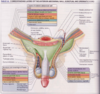

The perineum is the region of the trunk below the pelvic diaphragm and bounded by the pelvic outlet. It is subdivided by a line connecting the ischial tuberosities into 2 triangles that do not communicate. They are:

–anterior urogenital triangle(horizontal)

–posterior anal triangle (almost vertical)

What 3 things make up the anal triangle?

- Skin

- Superficial fascia (fatty layer that extends into the ischio-anal fossa)

- Anal canal surrounded by the external anal sphincter

The Ischio anal fossa is filled with fat & loose connective tissue. It is bordered by skin, gluteus maximus, obturator internus and fascia, levator ani and fascia, and external anal sphincter.

On the lateral wall is the…………… containing the…………….

Pudendal canal

pudendal nerve & vessels

Crossing the ischioanal fossa are the…………………..

inferior rectal nerves and vessels (branch from pudendal n. and internal pudendal a. and v. at the sciatic notch)